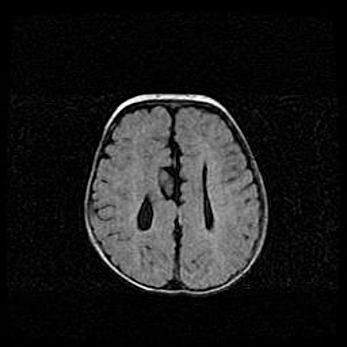

Наружная гидроцефалия с возможной атрофией височных областей.

Возраст: 28 дней

Вес: 3670 г

Пол: мужской

Окружность головы: 38 см

Срок гестации: 40 недель

Гидроцефалия головного мозга у новорожденных – это заболевание, которое характеризуется скоплением избыточного количества спинномозговой жидкости в желудочковой системе головного мозга в результате затруднения её перемещения от места выработки к месту поглощения в кровеносную систему или вследствие нарушения абсорбции. При открытой наружной форме гидроцефалии у новорожденных расширяются и переполняются субарахноидные пространства.

При нормотензивных  формах,  которые,  как  правило,  являются  следствием  перенесенных ишемических  повреждений  паренхимы  мозга,  возможно  сочетание микроцефалии  с нормотензивной гидроцефалией. В основе данных изменений лежит атрофия больших полушарий с преимущественной  локализацией  в  лобно-височных  областях.